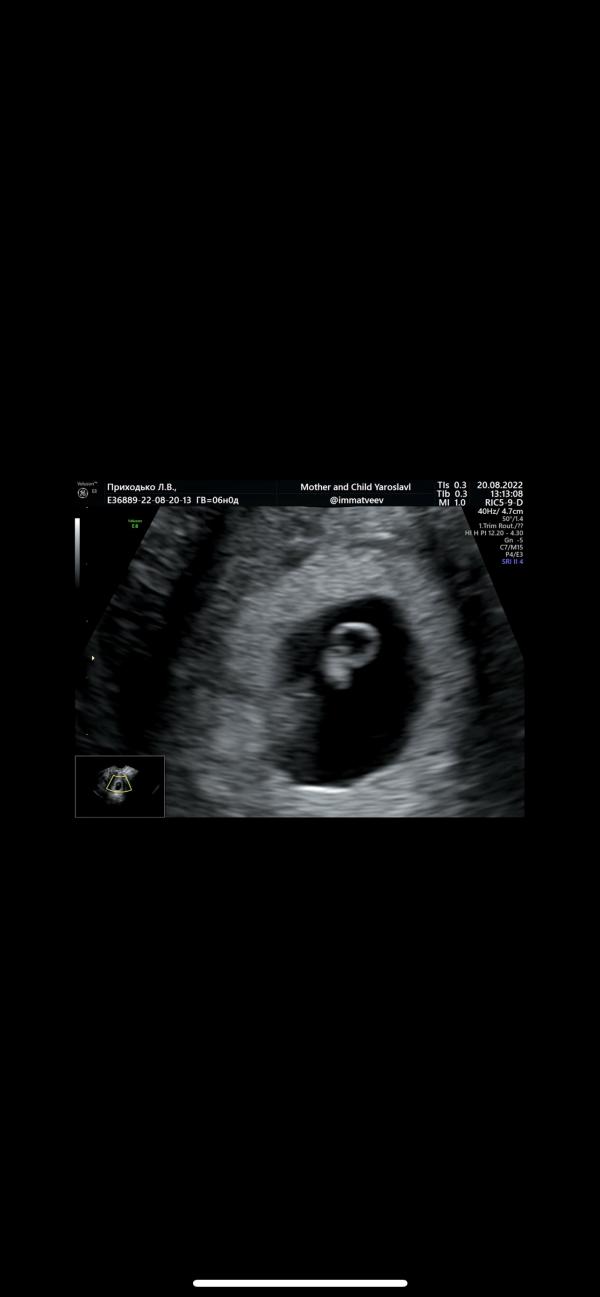

Сегодня ровно 6 недель

Попала я к чудесному врачу Матвееву И.М «мать и дитя» г.Ярославль

Сегодня я услышала стук сердца человека, который уже кстати целых 4 мм🥰

116 ударов в минуту